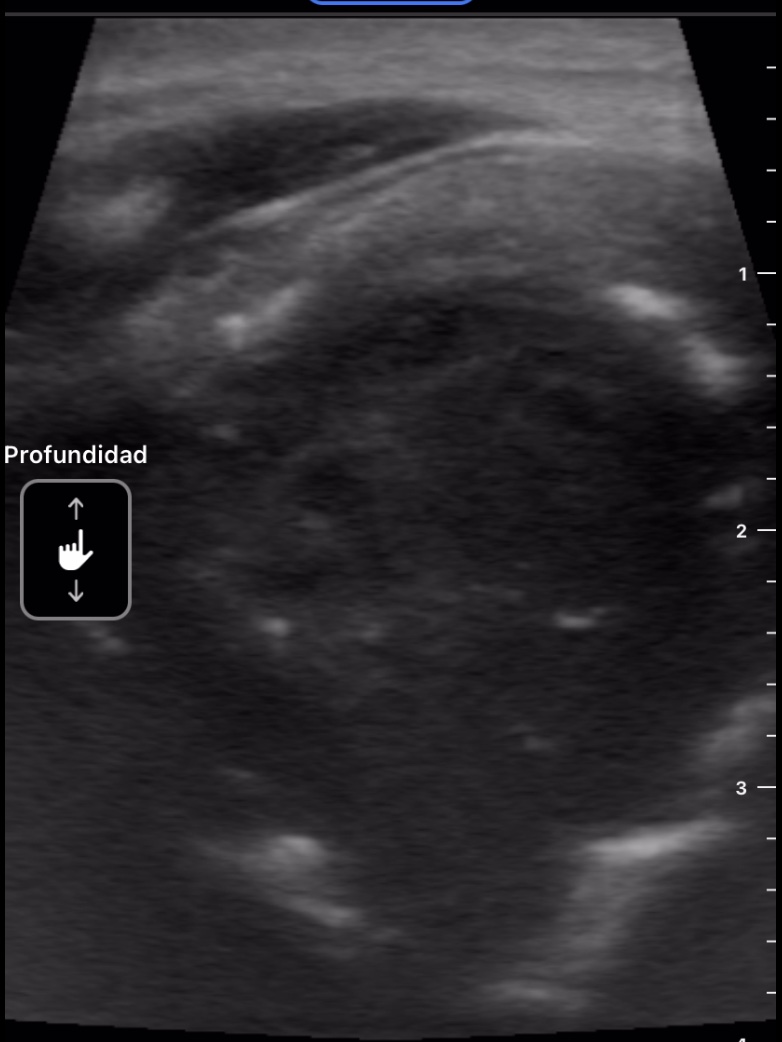

Se decide realizar ecografía clínica con ecógrafo de bolsillo para poder orientar caso, donde se aprecia tumoración de gran tamaño hipoecoica, heterogénea, con calcificaciones de pequeño tamaño en su interior, dependiente de lóbulo tiroideo derecho, sin poder definir límites inferiores, y sin poder localizar la vena cava inferior pero visualizando imagen de vena trombosada junto al istmo.

Ante la sospecha de cáncer de tiroides y la visualización de trombosis venosa que probablemente corresponda a vena cava inferior por la localización se deriva a Urgencias de Hospital de referencia, describiendo hallazgos y sospecha diagnóstica.